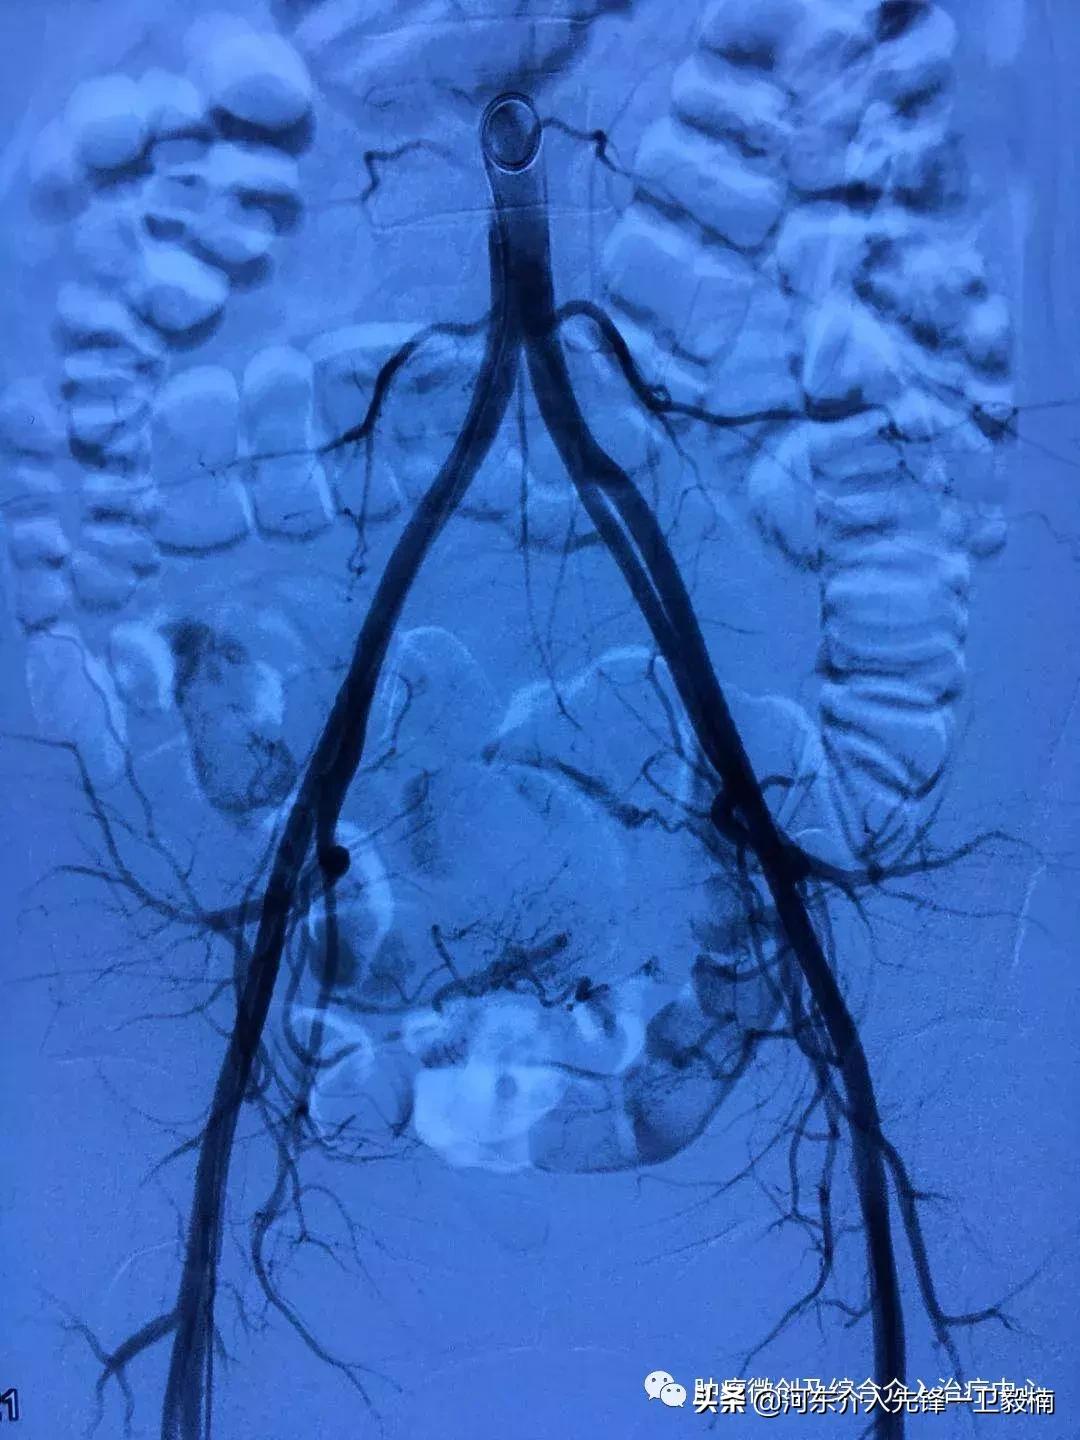

术中造影:子宫肌瘤的介入治疗原理是:将子宫肌瘤的血管堵住,让子宫肌瘤萎缩坏死,达到切断营养供应饿死肌瘤的目的。手术全程无任何痛苦,术后仅有一个针眼。